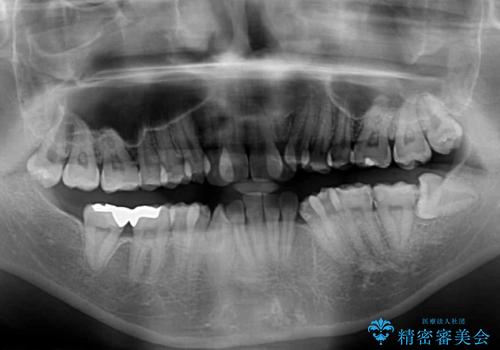

上顎の左右側切歯(前から2番目)が裏側に隠れいてる状態で、咬み合わせや清掃性に大きな問題が認められました。

左下に八重歯があったそうですが、当時は矯正治療を行うことを考えていなかったため、抜歯してしまったとのことでした。

叢生が著しいため、左下以外の第一小臼歯3本を抜去し、目立たないワイヤー装置にて矯正治療を行うこととしました。